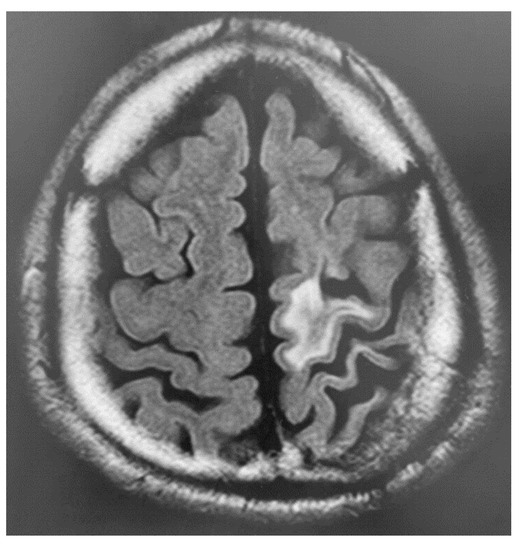

2.1. Case 1

2.2. Case 2